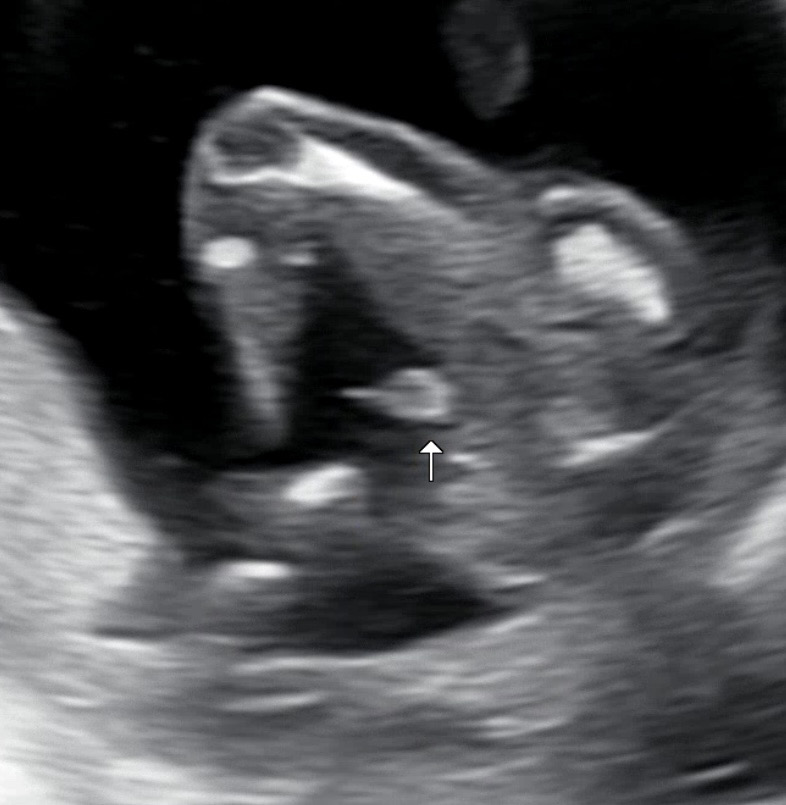

16주 0일 초음파에요 너무 확실한 아들...! 동생이 몇일 전 딸을 낳아서 같이 예쁘게 공동육아하면서 키우고싶어서 딸을 원하긴 했으나 건강한 아들이더라구요..ㅎㅎ 남자 형제가 없어서요ㅠㅠ 아들의 장점을 알려주세요!